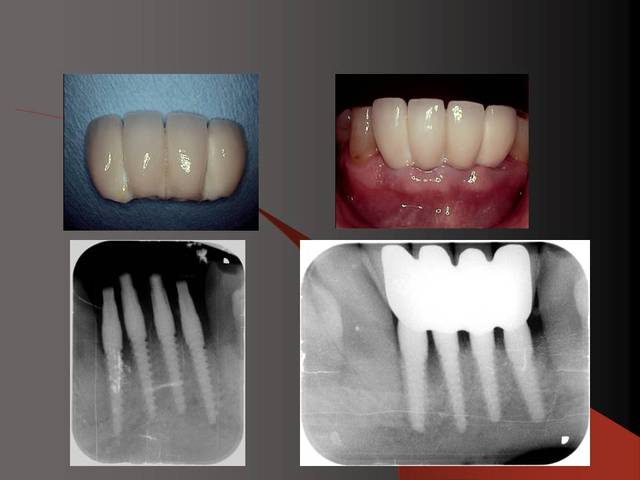

Photos d'un cas d'extraction implantation immédiate, stabilité primaire (de mémoire) assez élevée.. 60/70 N ..démontage du gingiva clips et du shuttle, pilier serré 40N, couronne procera

Merci pour le cas, bien fait. Belle présentation photo.

Le contour gingival est net, belle guérison, c'est à combien de semaine ?

Je vois un peu de ciment sur la radio finale, attention, c'est pas bien pour les tissus.

Oui je sais pour le ciment... j'utilise d'ailleur ce cas et cette radio dans une présentation pour mettre en garde sur le risque au moment du scellement de voir du ciment fuser sous la limite prothétique vers la col de l'implant..galère à éliminer...Personnellement je préfere plutot utiliser des piliers à usiner (maintenant disponibles voir shop online pour photos) au lieu des strandarts meme si il y a deux hauteurs/col implantaire en 1 et 3mm aujourd,hui disponibles..A l'époque de ce cas il n'y avait que les 1 mm et la limite est un "poil" trop profonde.

La pose de la couron nec'est faite 8 semaines apres l'extraction implantation immédiate, la particularité de ce systeme permet de ne pas démonter le shuttle ni la gingivaclip pour l'empreinte..je pense que ca aide bien à la qualité gingivale...radio controle ci jointe